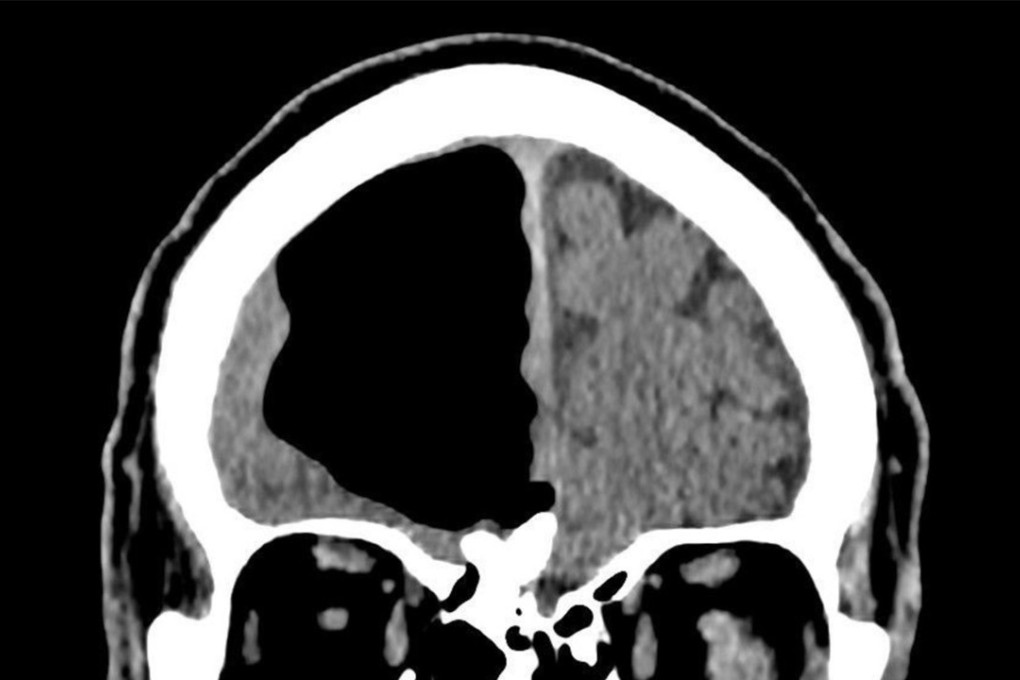

The man’s air cavity in his head measured almost 9cm at its widest point